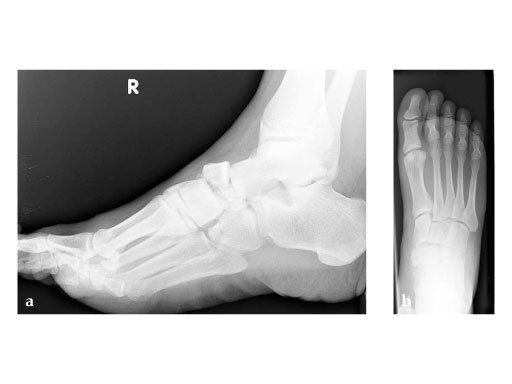

41-year-old male with a motor vehicle accident

Case provided by Thomas Tarquinio, Jackson, US